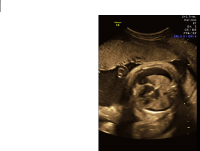

Hydrothorax

Hydrothorax axial chest